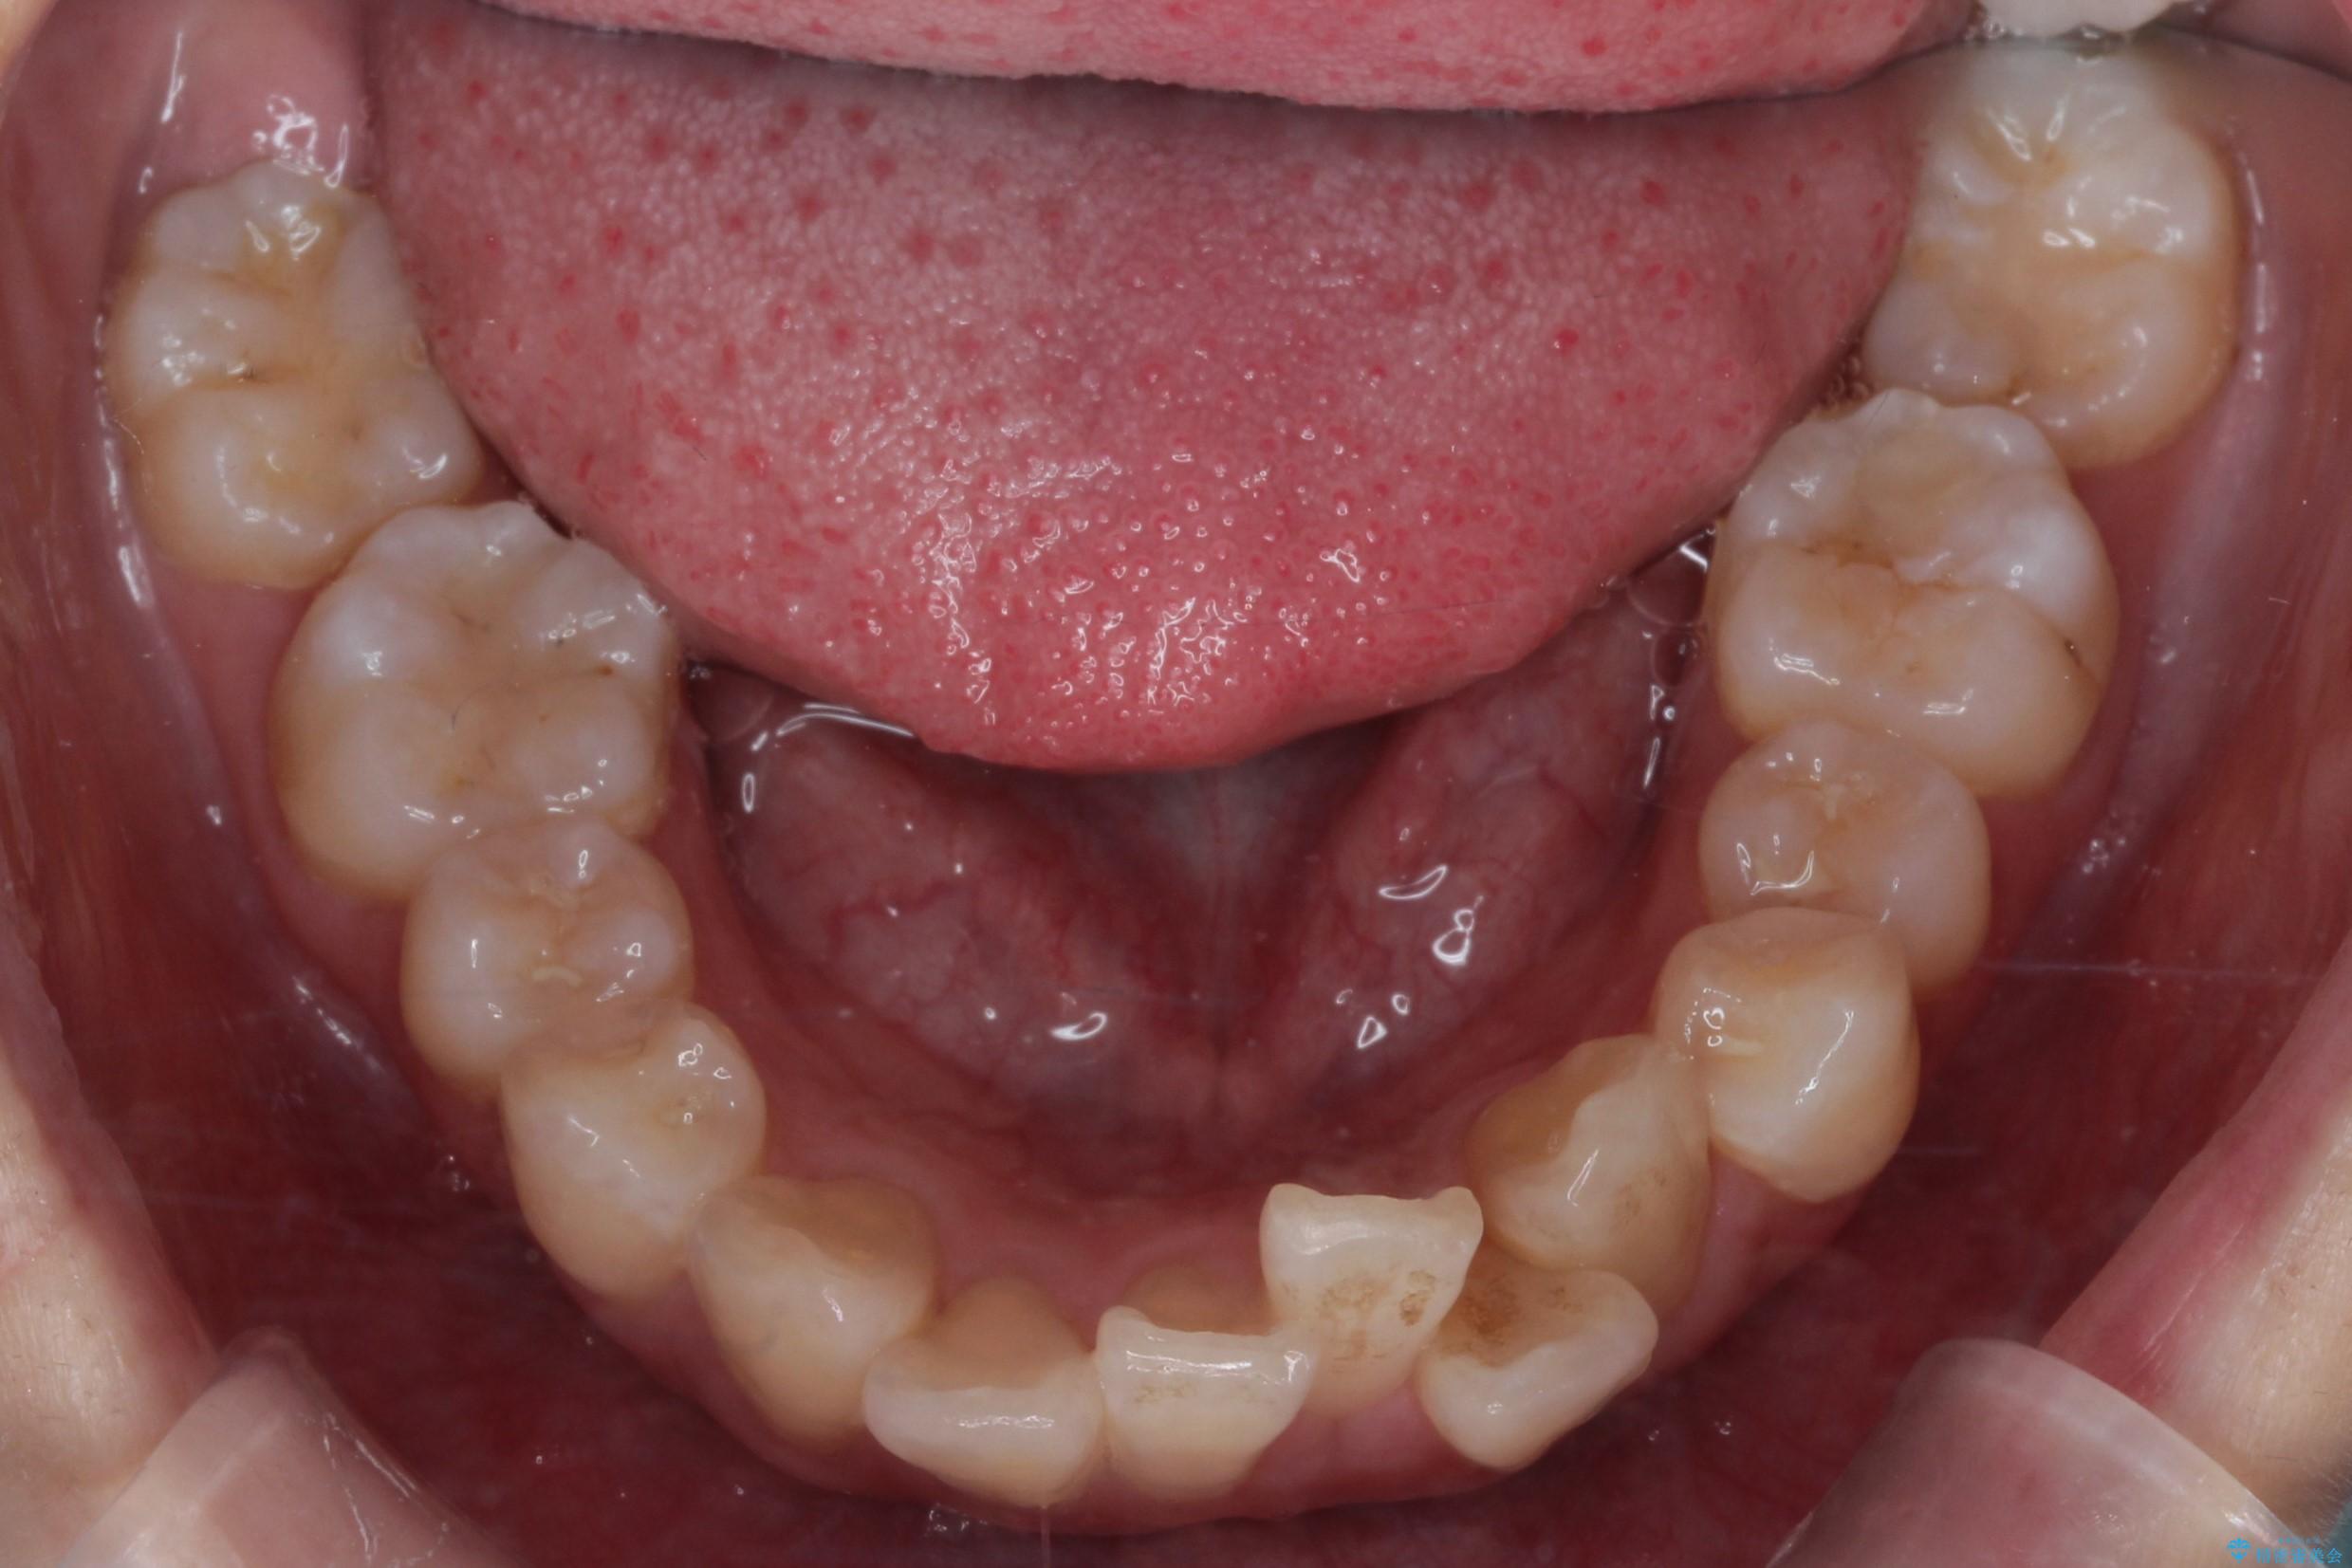

- 八重歯(叢生)と、上下の歯の中心線(正中)がずれていることを主訴にご来院されました。精密な検査の結果、歯列全体のスペースが大幅に不足しており、八重歯を正しい位置に配列し、正中のズレを改善するためには、上下左右の第一小臼歯を抜歯する必要があると診断。装置には、目立ちにくい審美ワイヤーを使用し、見た目を気にせず、機能性と審美性が完璧に整った咬み合わせを目指す治療計画を立案しました。

今回の矯正治療では、まず計画通り上下左右の小臼歯4本を抜歯し、八重歯や正中のズレを解消するための十分なスペースを確保しました。装置には、目立ちにくい白いブラケットとワイヤーを使用した審美ワイヤー矯正を採用。

抜歯によってできたスペースを利用し、

八重歯: 突出していた八重歯を歯列内に誘導し、デコボコを解消しました。